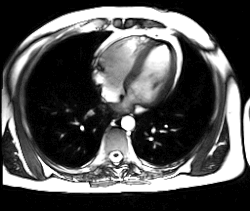

Магни́тно-резона́нсная томогра́фия (МРТ) — способ получения томографических медицинских изображений для исследования внутренних органов и тканей с использованием явления ядерного магнитного резонанса. Способ основан на измерении электромагнитного отклика атомных ядер, находящихся в сильном постоянном магнитном поле, в ответ на возбуждение их определённым сочетанием электромагнитных волн. В МРТ такими ядрами являются ядра атомов водорода, присутствующие в огромном количестве в человеческом теле в составе воды и других веществ[1].

МРТ не использует рентгеновские лучи или ионизирующее излучение, что отличает его от компьютерной (КТ) и позитронно-эмиссионной томографии. По сравнению с КТ, процедура МРТ более шумная и часто занимает больше времени, к тому же обычно требуется нахождение объекта в узком тоннеле. Кроме того, люди с некоторыми медицинскими имплантатами или другим несъёмным металлом внутри тела могут быть не в состоянии безопасно пройти МРТ.

Томография позволяет визуализировать с высоким качеством головной, спинной мозг и другие внутренние органы. Современные технологии МРТ делают возможным неинвазивно (без вмешательства) исследовать работу органов — измерять скорость кровотока, тока спинномозговой жидкости, определять уровень диффузии в тканях, видеть активацию коры головного мозга при функционировании органов, за которые отвечает данный участок коры (функциональная магнитно-резонансная томография — фМРТ).